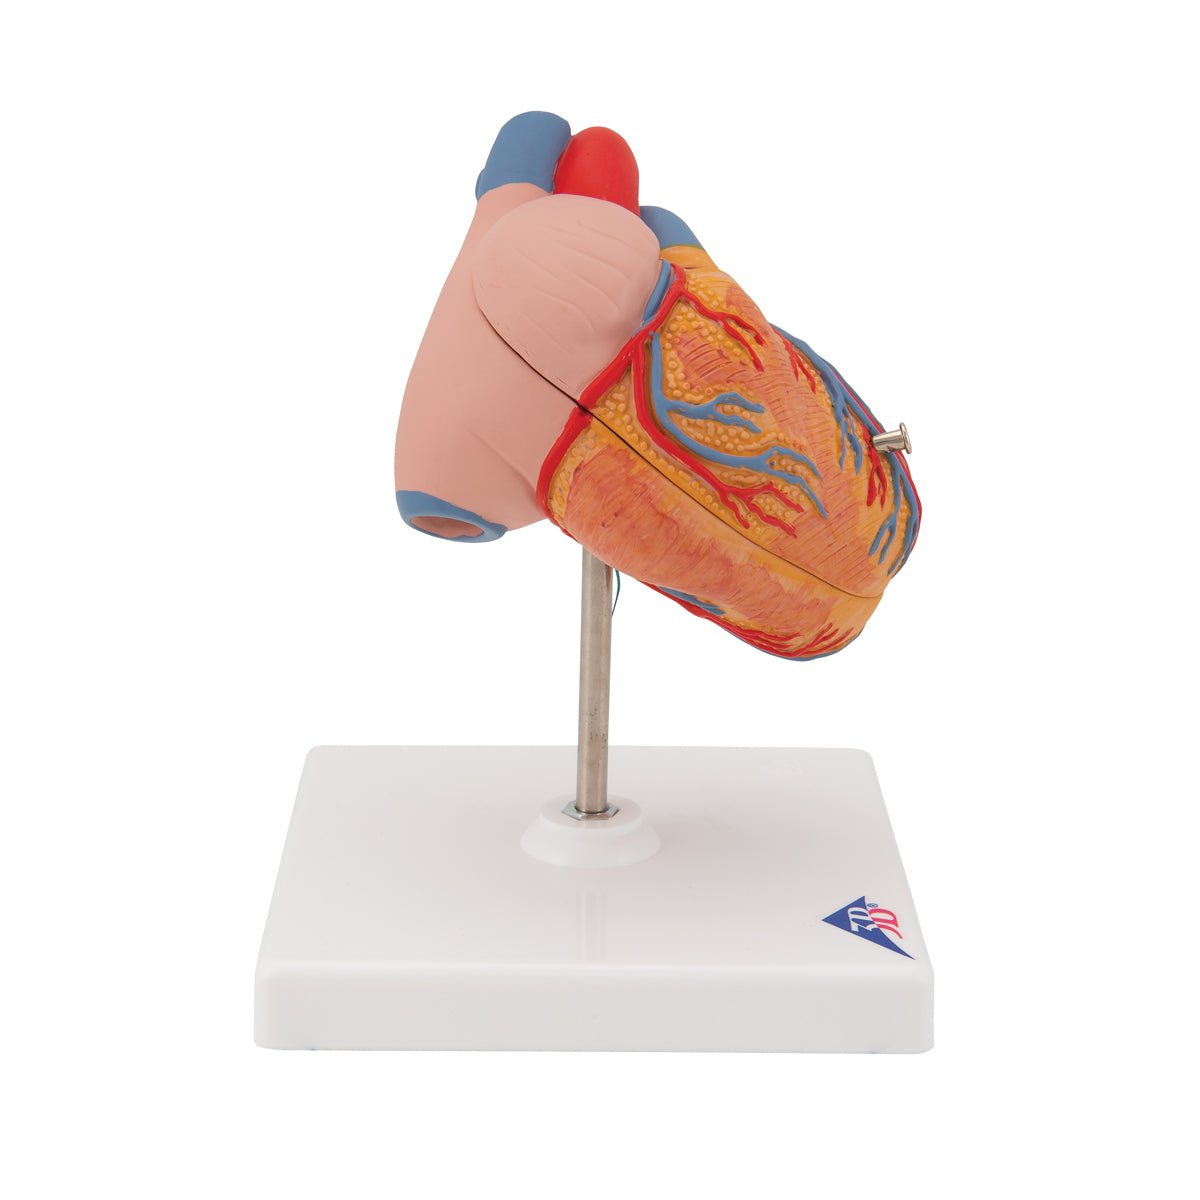

Selling anatomical models is the mainstay of eAnatomi, although we also spend a lot of resources developing our own anatomical materials such as posters. Anatomical models are used for various purposes and can show both defined tissues, organs and organ systems. Are you looking for a simple model of bone tissue or perhaps an advanced torso model based on MRI technology, you can find it all at eanatomi.com.